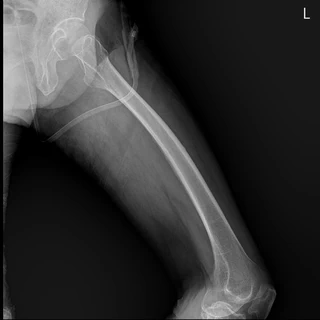

이 프로젝트는 의료 영상(DICOM) 데이터를 효율적으로 시각화하고 분석하기 위한 웹 기반 플랫폼을 개발하는 것을 목표로 합니다.

의료 인공지능 연구에서 생성된 모델을 실제 임상 환경에 통합하기 위해, AI 진단 결과와 원본 영상을 동시에 비교·검토할 수 있는 인터페이스를 구현했습니다.

- 🩻 DICOM 뷰어

다중 프레임(CT/MRI) 이미지 지원, 확대·축소·이동 기능, Window Level 조정 - 📏 거리 측정 도구

픽셀 간격 메타데이터를 이용한 mm 단위 정밀 거리 측정 - 🤖 AI 예측 결과 시각화

PyTorch 기반 딥러닝 모델의 예측 결과를 Bounding Box로 오버레이 - 🔄 결과 비교 모드